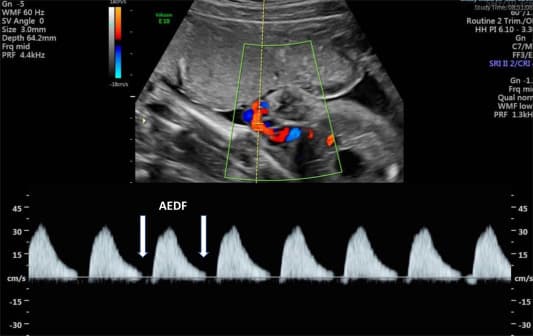

A specialized Doppler scan during pregnancy to assess fetal blood circulation, placental health, and umbilical cord flow.